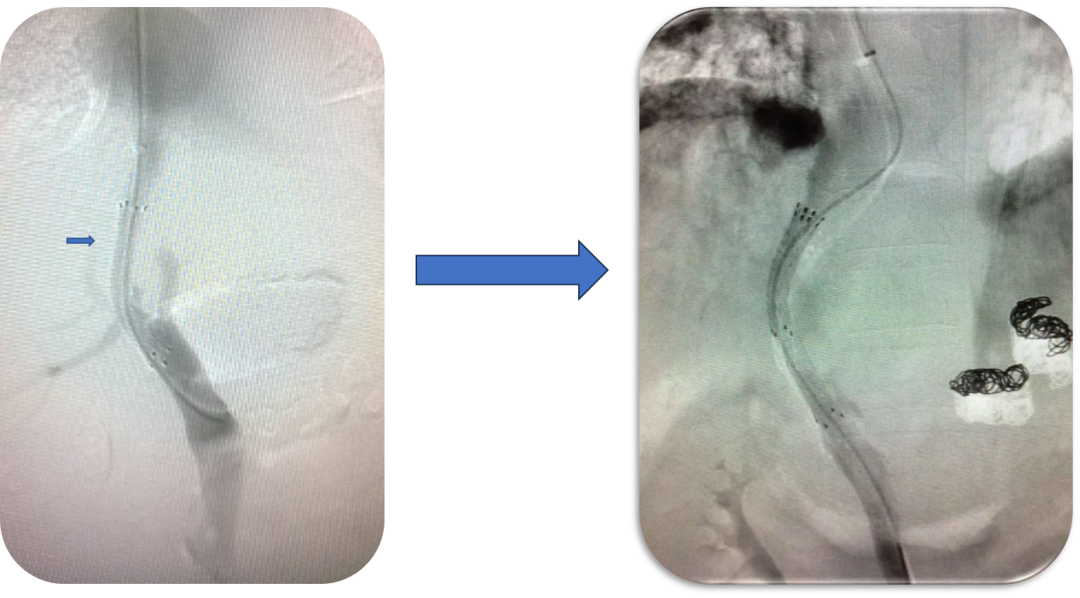

支架与穿刺路径优化

早期:采用裸支架 + 覆膜支架对接,易发生再狭窄;

穿刺策略:初期多选择门静脉右支(操作相对简单),但常导致分流道成角、盖帽,再狭窄率高;后期转向左支穿刺,路径更直,长期通畅率显著提升。

初期TIPS(裸支架—覆膜支架)

初期TIPS(技术的挑战)

门静脉右支穿刺

门静脉左支穿刺